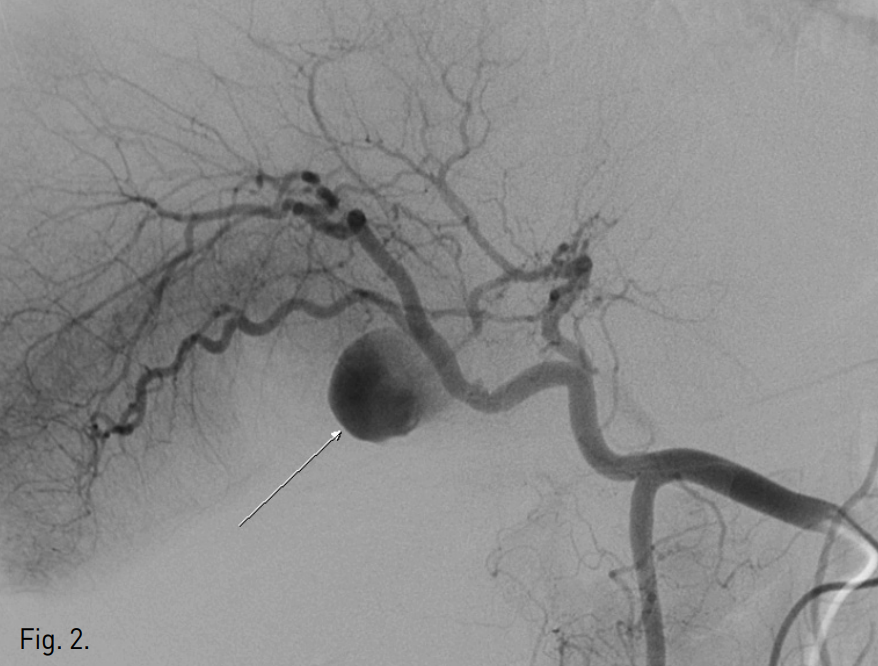

복부 컴퓨터단층촬영상 우측 간동맥 기원으로 생각되는 2.8cm 크기의 가성동맥류가 관찰되고 가성동맥류 주위에 complicated fluid collection과 air bubble들이 있으며, 간주위 공간과 오른쪽 가로막하 공간에도 complicated fluid collection이 있음(Fig. 1). 총간동맥 혈관조영술상 제 4 간분절(S4)로 가는 중간간동맥에서 기시하는 가성동맥류가 있으며 동맥류 안으로 조영제가 차 들어가는 것이 확인됨 (Fig. 2).

Fig. 2

Common hepatic angiography shows the pseudoaneurysm (arrow) developing at a branch of the middle hepatic artery.